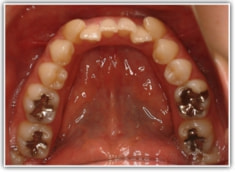

治療前

修復歯、補綴歯もあります。下顎8番が水平埋伏しています。